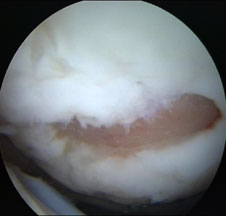

Artroscopia arata repararea tesuturilor la sase saptamani.

a.

b.

Fig.30. Cartilajul reparator la 6 luni dupa microfracturare ( a, b).